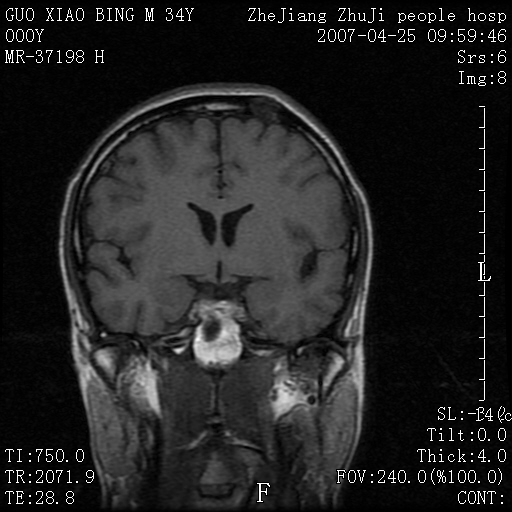

以下是引用qiuleiyu在2007-4-27 16:41:00的发言:[br]ct左侧额顶部囊性膨胀性骨质破坏,边缘有轻度硬化,其内示多发点条状高密度。[br]mri;t1低信号,t2明显高信号。界清。增强后明显强化。[br]综合考虑;颅内血管瘤。上传该病例,目的在于加深印象,共同学习。[br]骨血管瘤好发于颅骨及椎体。为良性肿瘤。组织学上分海锦型及毛细血管型。前者多见。[br]颅血管瘤典型影像学表现;[br]1,平片;类圆形骨质破坏,边缘硬化,内示中央向周边年轮状辐射(残存增粗骨小梁)。[br]2,ct;颅内板障内膨胀骨质破坏,边缘硬化,内示密集点状及放射状骨针影。[br]3,mr;t1、t2高信号。该病例t1不高可能与血流较丰富有关。边缘低信号。增强明显强化。[br]鉴别;[br]1,脑膜瘤;主要累及内板,与血管瘤发生于板障不同。颅板骨质增生硬化,与颅内垂直放射状骨针。与血管瘤日光放射状不同。增强可见脑膜尾征。[br]2,嗜酸性肉芽肿;起自板障溶骨性骨质破坏。内无点状及放射状高密度影。边缘硬化不明显。局部可有骨膜反应。[br]3,转移性肿瘤;溶骨破坏边缘模糊,无硬化边。发展迅速。有原发肿瘤史。可多发。可出现软组织块。[br]4,单发骨髓瘤;发病年龄较大,临床可能全身骨质疏松,骨痛。免疫球蛋白增高。部分病例本周氏蛋白可增高。可有边缘硬化,然内无点状高密度影。[br]